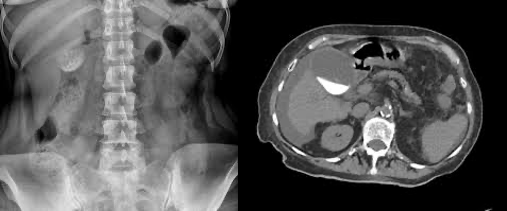

기종성 쓸개염

• 정의: 급성 담낭염으로 시작해 담낭벽 허혈 및 괴사로 진행된 경우

• 진단 : CT 또는 초음파상 담낭내 공기, 담낭벽 기체성 고리 형성

• 치료 : 응급 쓸개절제술 + 항생제